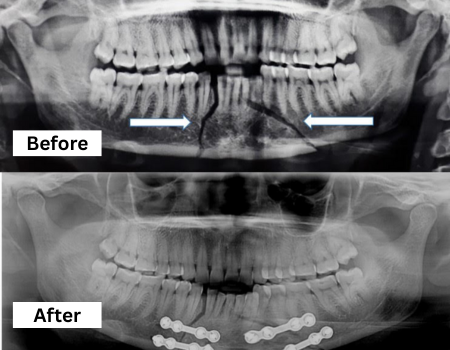

Facial Trauma Treatment

Expert management of facial injuries including fractures and soft tissue repair, ensuring functional restoration and optimal cosmetic outcomes.

Orthognathic Surgery

Orthognathic surgery corrects jaw and lower face structure, growth, and airway issues like sleep apnea and TMJ disorders , malocclusionproblems due to skeletal disharmonies.